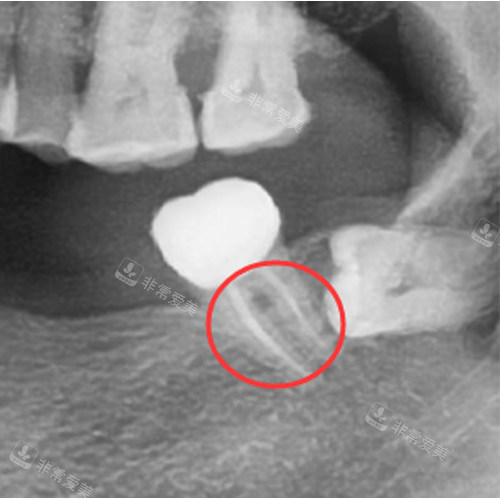

根管治疗改善图